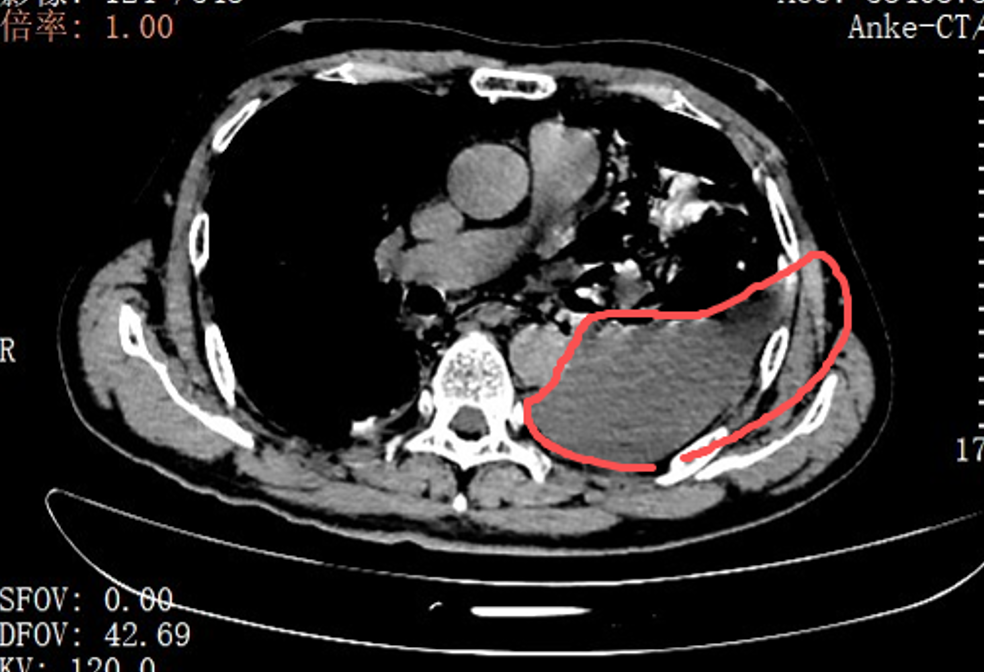

红圈区域是食物残渣、消化液破入食管

手术团队拿着吸引器,一点点清理、冲洗,花了很长时间才将胸腔里的每一点食物残渣都清干净。随后,团队找到了食道下段那道长达10公分的裂口,用可吸收线小心翼翼地完成了分层修补。